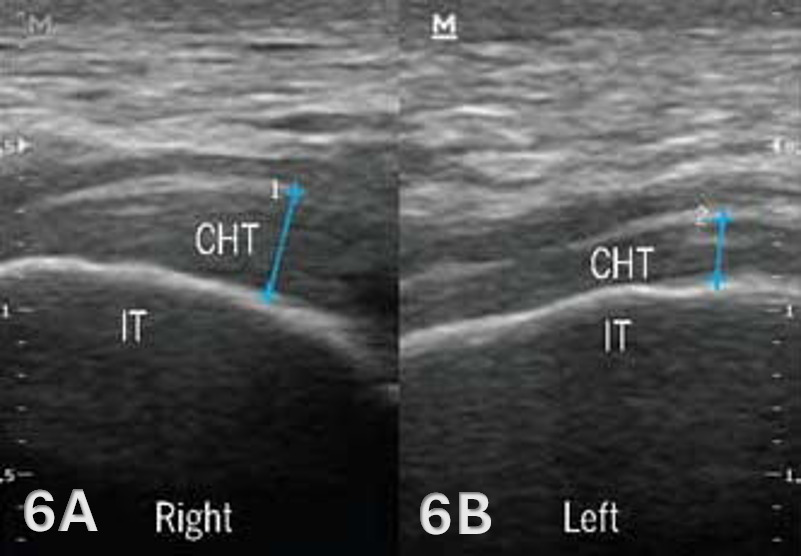

Pathologic Findings in Lateral Proximal Hamstring Tendon and Muscle Injury

Disruption of fibrillar pattern in partial tears and ruptures. Proximally, it is important to determine if the injury is a free-tendon injury or purely a myotendinous injury.20

Associated effusion.